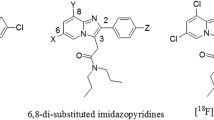

Utilizing a bis(thiosemicarbazone) backbone, a fluorescent ATSM-FITC conjugate was synthesized. Its copper complex, Cu(ATSM-FITC) was thoroughly tested as a biosensor for H2S. The same ATSM-FITC ligand was quantitatively labeled with [64Cu]CuCl2 to obtain a radioactive [64Cu][Cu(ATSM-FITC)] imaging probe. Biodistribution and positron emission tomography (PET) imaging studies were performed in healthy mice and neuroinflammation models.

The Cu(ATSM-FITC) complex reacts instantly with H2S to release CuS and becomes fluorescent. It showed excellent reactivity, sensitivity, and selectivity to H2S. Endogenous H2S levels in living cells were successfully detected by fluorescence microscopy. Exceptionally high brain uptake of [64Cu][Cu(ATSM-FITC)] (> 9% ID/g) was observed in biodistribution and PET imaging studies. Subtle changes in brain H2S concentrations in live mice were accurately detected by quantitative PET imaging. Due to its dual modality feature, increased H2S levels in neuroinflammation models were characterized at the subcellular level by fluorescence imaging and at the whole-body scale by PET imaging.